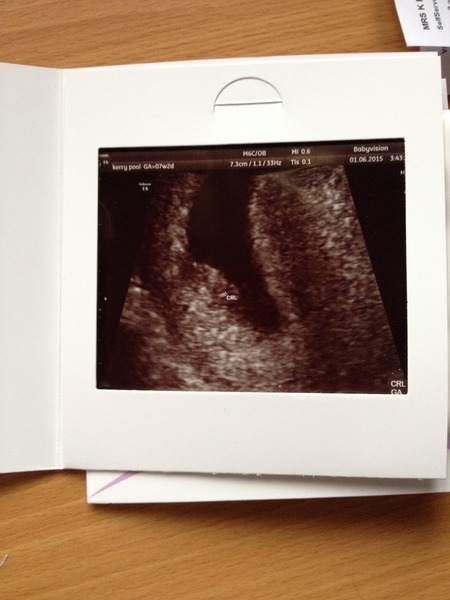

I've attached my scans - from 7+2, 8+6 and 10+2 - amazing how much Bean looks like a baby now rather than a blob. Bean was wriggling and moving around at the 10+2 scan, so cannot wait until the 12 week scan (at 12+2)

kep I thought I was 12+2 at the scan but turns out I'm 13 weeks Shock